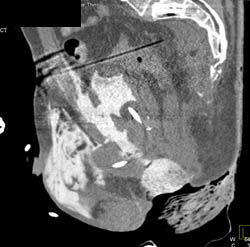

3D VRT Bone and Soft Tissue- See Disc Spaces